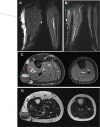

Klippel-Trenaunay Syndrome (KTS) is a rare genetic vascular disorder characterized by a limb affected by varicose veins, port wine stains, and hypertrophy of bone and soft tissue. It can also present with vascular malformations in the gastrointestinal tract, liver, spleen, genitourinary tract, and heart. We present a 27-year-old case of KTS diagnosed in adulthood associated with recurrent venous thromboembolism and gastrointestinal bleeding.